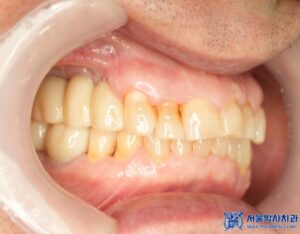

임플란트 수술이 끝나고 임플란트가 잘 고정된 후에는,

저희 서울박사치과 원내기공소에서 제작한

개인 맞춤형 보철물을 세팅해드렸습니다.

저희 기공소에는 10년 이상의 경력을 지닌

전문 치과기공사가 상주하여,

단순히 예쁜 보철물만이 아닌 퀄리티가 높은

기능적이고 편안한 보철을 제작해 드리고 있습니다.

특히 맞춤형 지대주를 제작하여 음식물 끼임을

줄이고 환자 개개인의 구강구조에 꼭 맞게

보철물을 제작합니다.

또한 고품질 재료를 사용해 내구성이 뛰어나고

심미성이 우수하며,

치료 마무리 후 사진입니다.

최종 보철물 세팅 이후 환자분께서는 불편함도 없었고,

교합 체크를 위해 다시 내원하셨을 때도

“음식 씹을 때 너무 편하고, 교합도 잘 맞는다”고

만족해하셨습니다.